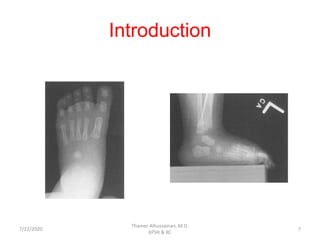

• Ossific development of the foot begins in utero.

• At birth, talus, calcaneus, cuboid, metatarsals, and phalanges are

ossified.

• The lateral cuneiform ossifies 4/12-20/12.

• The medial cuneiform ossifies at 24/12.

• The intermediate cuneiform ossifies at 36/24.

• The navicular ossifies last 3-5 yrs.